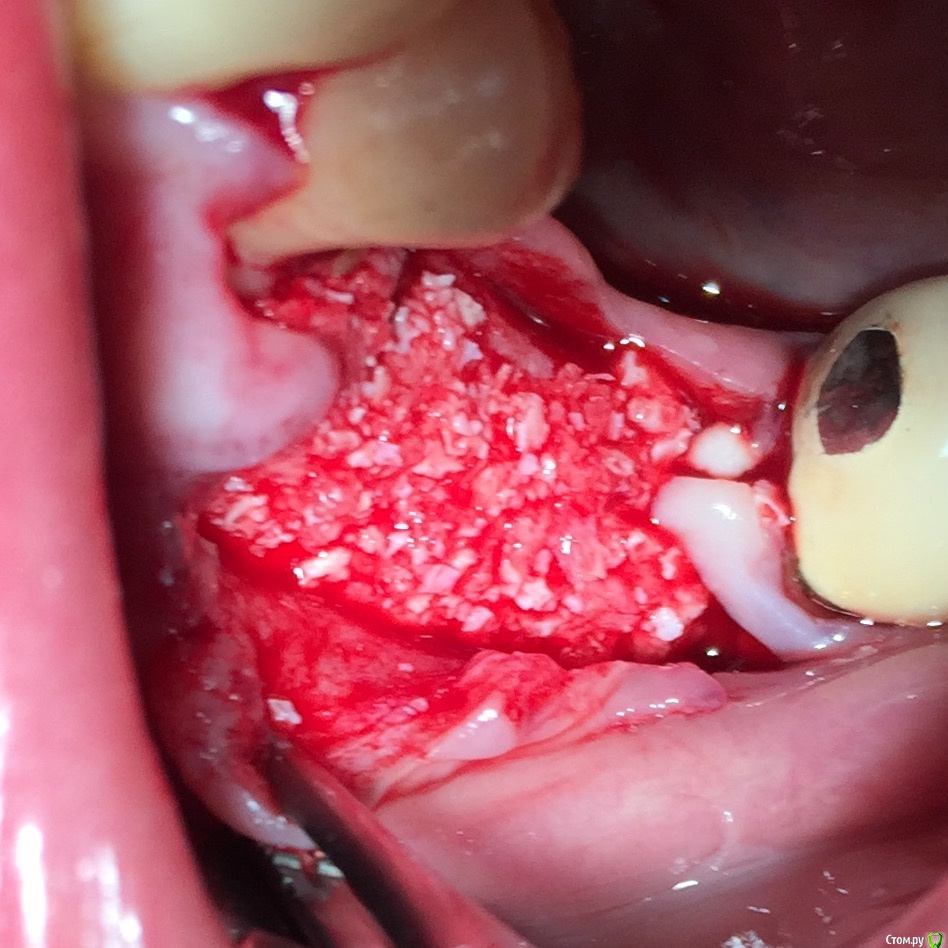

Глеб Митрофанов Опубликовано 12 сентября, 2015 Поделиться Опубликовано 12 сентября, 2015 (изменено) Решил потратить деньги , отложенные на Гамборену , приобрел набор для расщепления . Протестировал , понравилось . Особенно понравился пьезоаппарат , учитывая то , что впервые работал пьезо . За одно протестировал и джейловский гаджет для сбора кости , тоже понравился . Уже по обыкновению использовал A-PRF и I-PRF. Фото с телефона , обрезанные , на телефоне четче смотрятся. Изменено 12 сентября, 2015 пользователем Глеб Митрофанов 4 Ссылка на комментарий

АлинаК Опубликовано 17 сентября, 2015 Поделиться Опубликовано 17 сентября, 2015 Решил потратить деньги , отложенные на Гамборену , приобрел набор для расщепления . Протестировал , понравилось . Особенно понравился пьезоаппарат , учитывая то , что впервые работал пьезо . За одно протестировал и джейловский гаджет для сбора кости , тоже понравился . Уже по обыкновению использовал A-PRF и I-PRF. Фото с телефона , обрезанные , на телефоне четче смотрятся.Добрый день! Подскажите,пожалуйста,название набора и производителя(если можно) Ссылка на комментарий

Глеб Митрофанов Опубликовано 17 сентября, 2015 Автор Поделиться Опубликовано 17 сентября, 2015 Добрый день! Подскажите,пожалуйста,название набора и производителя(если можно) Мистер Кюрет , продает Имплант Ру Ссылка на комментарий